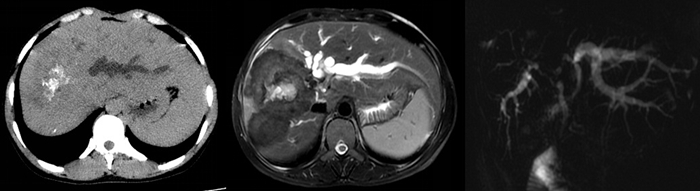

近日,医院肝胆外科收治了一名患晚期泡型肝泡虫病的年轻女性患者,主因“发现肝包虫病2年余,右上腹疼痛1月”于2019年06月24日入院。患者病情复杂,入院后予以完善相关检查,初步诊断为右肝泡型肝包虫病、梗阻性黄疸、低蛋白血症。患者肝功能极差,属肝叶切除手术的绝对禁忌症,入院初先予以了保肝消炎营养支持治疗。患者治疗一周后复查,患者的白蛋白仍低,胆红素极高,手术风险相当大,经全科室讨论后一致决定为患者进行PTCD减黄术。

7月2日在彩超室副主任兰晓蓉大力支持与引导下,陈见中主治医师为患者进行了彩色多普勒可视化引导PTCD(经皮肝穿刺胆道引流术)改良术减黄,最初引流胆汁为黑褐色,证明淤胆时间长,后转为黄色胆汁,图为引流后3天。

经PTCD引流,抗炎保肝营养支持等对症支持治疗,患者7月14日复查,经治疗后肝功能明显好转,可考虑手术治疗。7月15日下午,在医务科大力支持下于外二科学习室进行了MDT(多学科)讨论,医务科科长蒲光军、外二科主任喻定刚、麻醉科主任雍记智、重症医学科主任张泽奎、放射科副主任丁世荣、彩超室副主任兰晓蓉、消化内科省医院老师及主管医师陈见中对患者病情、术前准备、手术方案、术中可能出现的情况、术后转规进行了深入的讨论,为患者选择最优化的治疗方案。在放射科副主任丁世荣的大力支持下,为患者进行了肝脏3D重建、残肝体积测定,考虑患者残肝体积充够,拟定7月16日行肝右三叶切除术+肝管空肠吻合术。